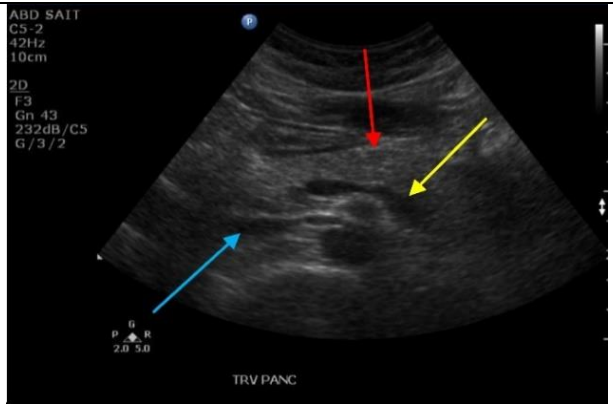

10

Q

Label the red, blue, and yellow arrows

A

Red: Body of pancreas

Blue arrow: IVC

Yellow: Splenic vein